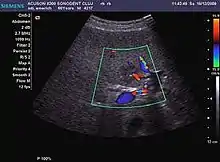

The ultrasound appearance is a well defined lesion, with very thin, almost unapparent walls, without circulatory signal at Doppler or CEUS investigation. The content is transonic suggesting fluid composition. The presence of membranes, abundant sediment or cysts inside is suggestive for parasitic, hydatid nature. Posterior from the lesion the acoustic enhancement phenomenon is seen, which strengthens the suspicion of fluid mass. They typically displace normal liver vessels but no vascular or biliary invasion occurs.

It is the most common liver tumor with a prevalence of 0.4 – 7.4%. It is generally asymptomatic but also can be associated with pain complaints or cytopenia and/or anemia when it is very bulky. It is unique or paucilocular. It can be associated with other types of benign liver tumors. Characteristic 2D ultrasound appearance is that of a very well defined lesion, with sizes of 2–3 cm or less, showing increased echogenity and, when located in contact with the diaphragm, a "mirror image" phenomenon can be seen. When palpating the liver with the transducer the hemangioma is compressible sending reverberations backwards. Doppler exploration reveals no circulatory signal due to very slow flow speed. CEUS investigation has real diagnosis value due to the typical behavior of progressive CA enhancement of the tumor from the periphery towards the center. The enhancement is slow, during several minutes, depending on the size of hemangioma and on the presence (or absence) of internal thrombosis. During late (sinusoidal) phase, if totally "filled" with CA, hemangioma appears isoechoic to the liver. Deviations from the above described behavior can occur in arterialized hemangiomas or those containing arterio-venous shunts. In these cases, differentiation from a malignant tumor is difficult and requires other imaging procedures, follow up and measurements of the tumor at short time intervals.[4]

It is a tumor developed secondary to a circulatory abnormality with abundant arterial vessels having a characteristic location in the center of the tumor, within a fibrotic scar. A radial vessels network develops from this level with peripheral orientation. The tumor's circulatory bed is rich in microcirculatory and portal venous elements. The incidence is higher in younger women and tumor development is accelerated by oral contraceptives intake. 2D ultrasound appearance is a fairly well-defined mass, with variable sizes, usually single, solid consistency with inhomogeneous structure. Rarely the central scar can be distinguished. Spectral Doppler examination detects central arterial vessels and CFM exploration reveals their radial position. CEUS examination shows central tumor filling of the circulatory bed during arterial phase and completely enhancement during portal venous phase. During this phase the center of the lesion becomes hypoechoic, enhancing the tumor scar. During the late phase the tumor remains isoechoic to the liver, which strengthens the diagnosis of benign lesion.